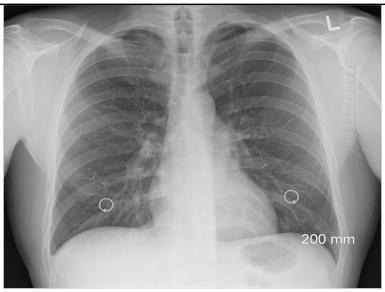

2.6.1. Test Procedure

The stress test involved simulating varying numbers of concurrent users querying the system. For each LLM, we executed 20 clinically relevant prompts, as shown in (Table A2) in the Appendix A. For each VLM, 10 different images with 2 prompts per image resulting in a total of 20 prompts per model were tested. The specific prompts used are listed in (Table A3) in the Appendix A. We tested user loads of 10, 20, 30, 40, 50, 75, 100, 125, and 150 users. In order to measure the robustness of the container as well as the robustness of JAVIS, this experiment queried the JAVIS back-end to measure the complete roundtrip response times. This approach ensured that the test accurately reflected real-world usage scenarios, including the overhead of back-end processing and model orchestration.

JAVIS supports multimodal LLMs or VLMs, allowing the integration of various image types (JPG, PNG, etc.). This enhancement significantly increases the system’s versatility in handling diverse clinical inputs, enabling more comprehensive and accurate patient interactions.